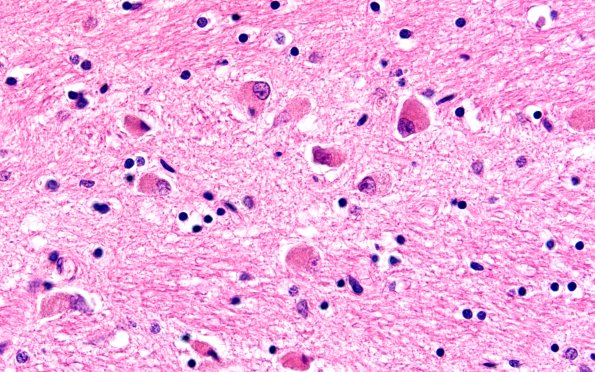

7E2 NCL (Case 7) Pons 60X H&E

Neurons of the basis pontis contain storage product. (H&E)